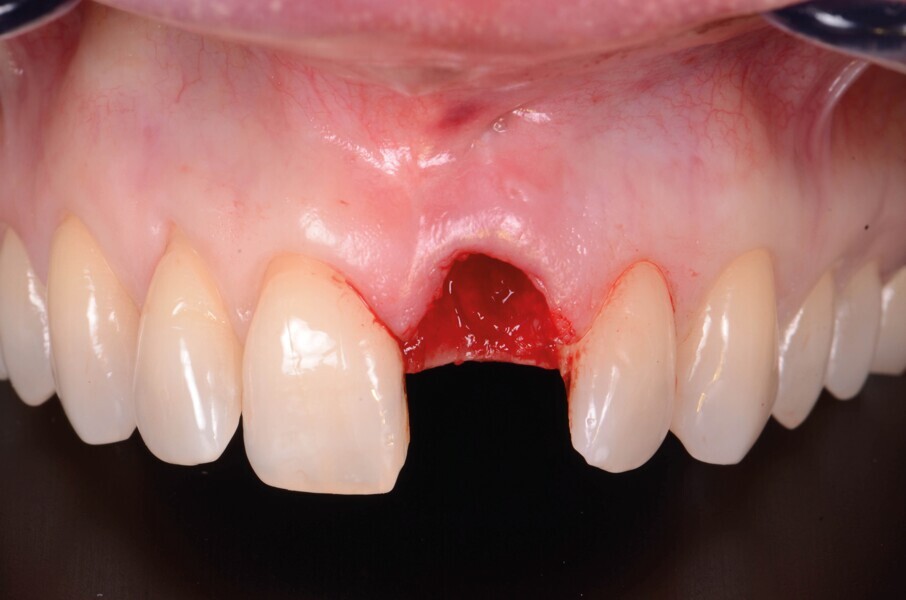

La dent 21 est extraite de la manière la moins traumatique possible à l’aide d’un périotome (Fig. 4). Elle est conservée dans du sérum physiologique afin de pouvoir l’utiliser comme restauration provisoire par la suite.

Fig. 4 : Extraction atraumatique de la dent 21.

Fig. 5a : Après l’extraction

Fig. 5b : Après l’extraction